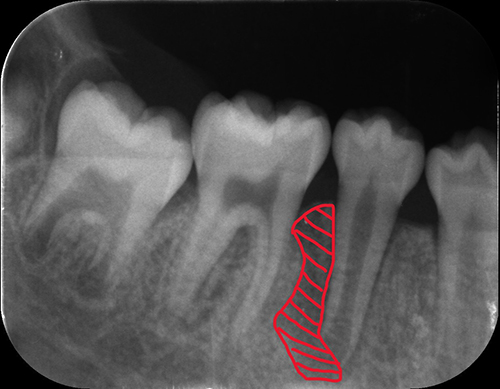

【初期】

【中期】

【完了】

この症例は、生え変わり前に根管に膿が溜まっていた(赤で示した部分)ため。

その部分の除去を行いました。

治療を早期段階で行ったことで歯根もしっかり伸びました。

初期:膿が陰になっている

中期:膿が除去できているが歯根が短い

完了:膿もなく歯根もしっかり伸びている